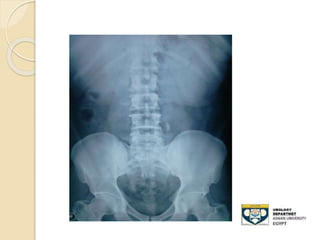

KUB film

 - Advantages:

◦ 80-90% of stones are radio-opaque

◦ Minimal radiation

 Disadvantages:

◦ Radiolucent stone

◦ Easy to miss mid-ureteral stones over the

sacrum

◦ Bowel gas can obscure its efficacy

◦ Cannot differentiate , Stones,Calcified LN

,

◦ Sensitivity: 50-70%

STONE MIDDLE THIRD URETER